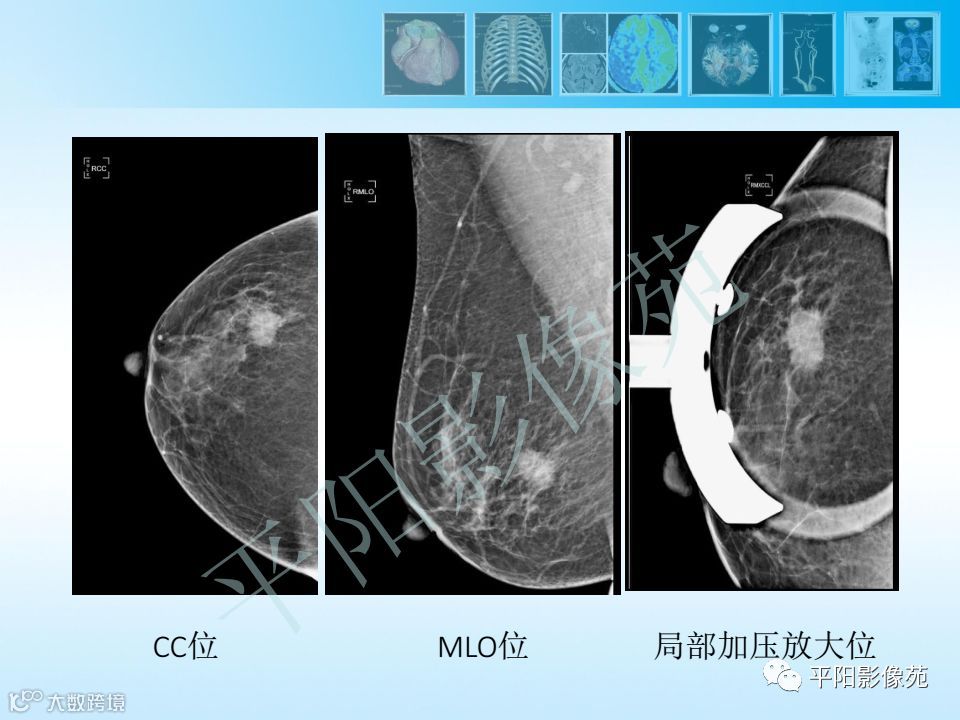

乳腺钼靶报告书写规范

乳腺钼靶报告书写规范 平阳影像苑